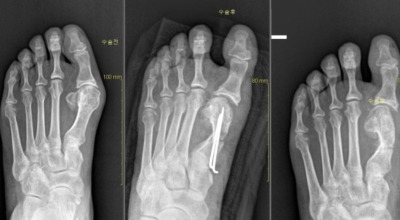

초기 단계에서는 건막류(두꺼운 혹)를 절제하는 건막류절제술을 시행합니다. 돌출된 건막류를 절제하여 각도를 교정하고, 짧아진 근육이나 연부조직을 늘려주는 비교적 간단한 수술입니다. 다른 발가락의 변형이 동반되거나 뼈의 과잉 성장이 심한 경우에는 뼈를 깎고 방향을 돌린 뒤 발가락이 똑바로 펴지도록 철사로 고정하는 교정절골술을 시행합니다. 양쪽 발이 모두 변형된 경우, 대개 한 번에 한쪽만 수술합니다.